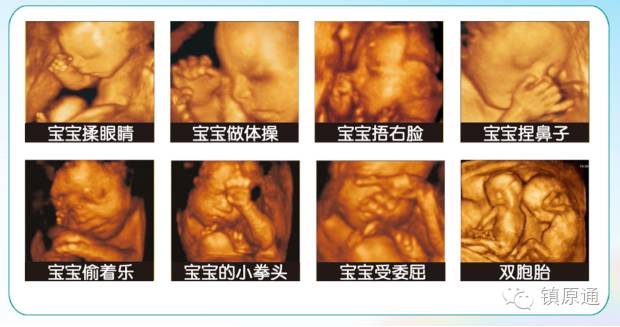

是立体动态显示的彩色多普勒超声诊断仪,可以进行胎儿头面部立体成像,可显示眼、鼻、口、下颌等状态,协助医生直接对胎儿先天畸形进行诊断,价格比普通彩超价格贵。

●四维彩超

四维彩超能够对胎儿进行动态、立体超声检查,显示胎儿的面部、各器官的发育情况,甚至胎儿在母体里的状态也可以观察到;对胎儿畸形,如唇裂、腭裂、骨骼发育异常等能早期诊断。另外还能制作成光盘,让宝宝拥有最完整的0岁相册,留下永久的记忆。

过去使用的B超设备只能检查胎儿的一些生理指标,而四维彩超还能对胎儿的体表进行检查,如唇裂,脊柱裂,大脑、肾、心脏、骨骼发育不良等情况,以便尽早的进行治疗,生个聪明健康的小宝宝。四维彩超能进行宫内写真,让准妈妈看到宫内宝宝的一举一动,亲身体会到宝宝的笑容相貌!而且四维彩超可以把宫内四维彩超宝宝的动态刻录成dvd作为宝宝的0岁写真!永久留念!